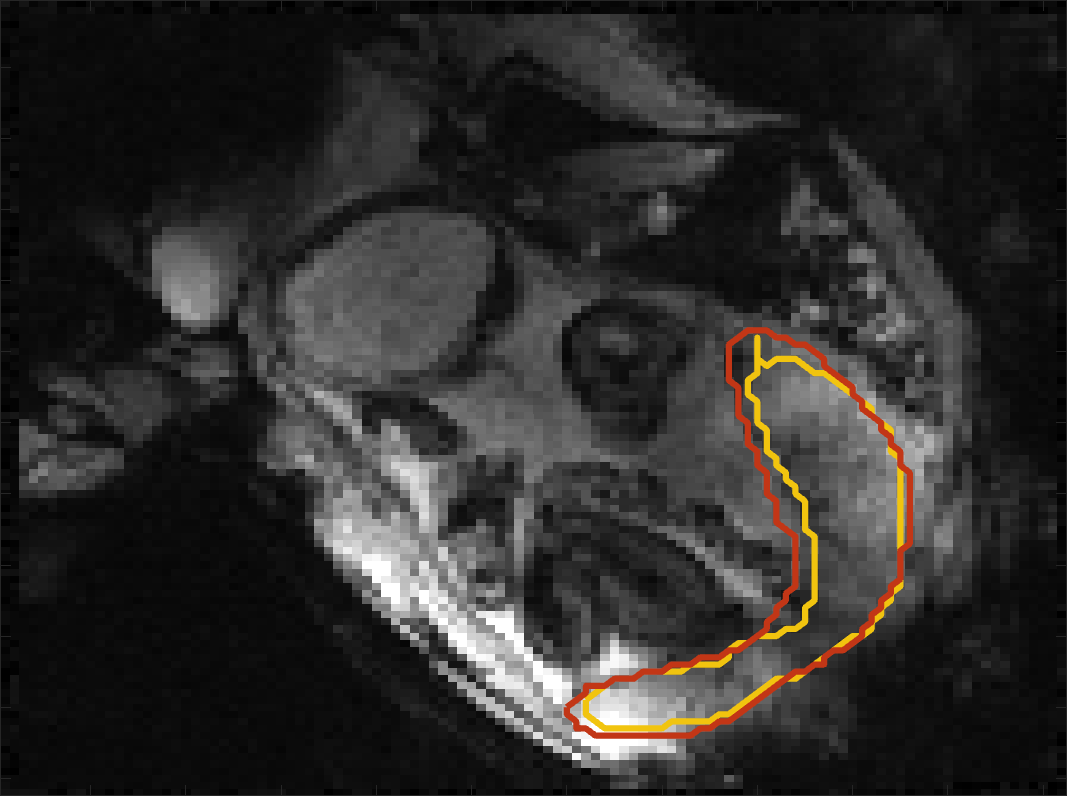

Figure 4 compares the predicted label maps with ground truth on subjects with increasing Dice scores using the BW-CE model. The model accurately identifies the location of the placenta, but in the worst cases misses boundary details.

BOLD Time Series Evaluation

Figure 5 presents example predicted segmentations at multiple points in the BOLD MRI time series for subjects. The predicted segmentations are robust to large fetal deformations and placental signal changes. Figure 6 (top) presents distributions of Dice score between predicted label maps of consecutive frames in the BOLD time series for all subjects in the test set. Distributions have high medians (Dice ) for all but one case, with high density at high Dice scores (Dice ). Dice differences are highly affected by fetal and maternal motion that cause placental deformation. We visually verified that modest drops in Dice () were mainly due to fetal motion, but subjects had a small number of frames with large drops (Dice ) that were caused by errors in the produced label maps. Figure 6 (bottom) shows D models of failed segmentations from two subjects from frames with Dice . Our model omitted parts of the placenta for Subject and added a large region for Subject . In practice, these failures ocurred in a small number of frames, of frames for Subject and of frames for Subject . Overall, predicted label maps are consistent between consecutive volumes of the MRI time series, achieving a Dice of and a BOLD difference of . The small differences between the relative mean-BOLD values suggest these produced segmentations may be suitable for research studies assessing placental function.